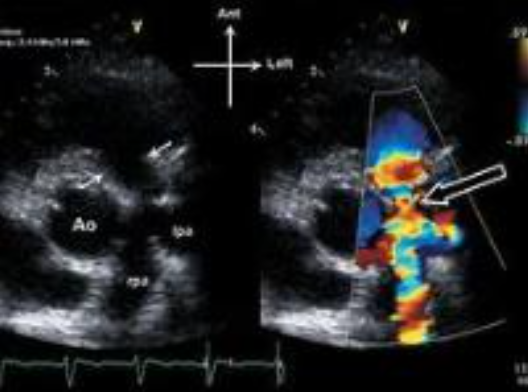

What are the echo findings?

A

• thickening if the PV leaflets with systolic doming

• RV hypertrophy due to RV pressure overload = increased afterload

• flattening if the IVS due to the RV pressure overload *D shaped LV (can be visualized in PSAX)

• RA enlargement

• RV failure in the later stages of PS

• post-stenotic dilatation of the MPA due to the high velocity PS jet striking the PA wall *similar to AS

Explain how to assess with Doppler

similar to AS, assess:

• peak velocity

• max & mean PG

• PVA

via the continuity equation

• CW focus in the PV; acquire the PV peak velocity & the VTI

• PW gate in the RVOT; acquire the RVOT peak velocity & VTI

*For a quick PG, utilize the modified Bernouli’s equation: PG = 4V2